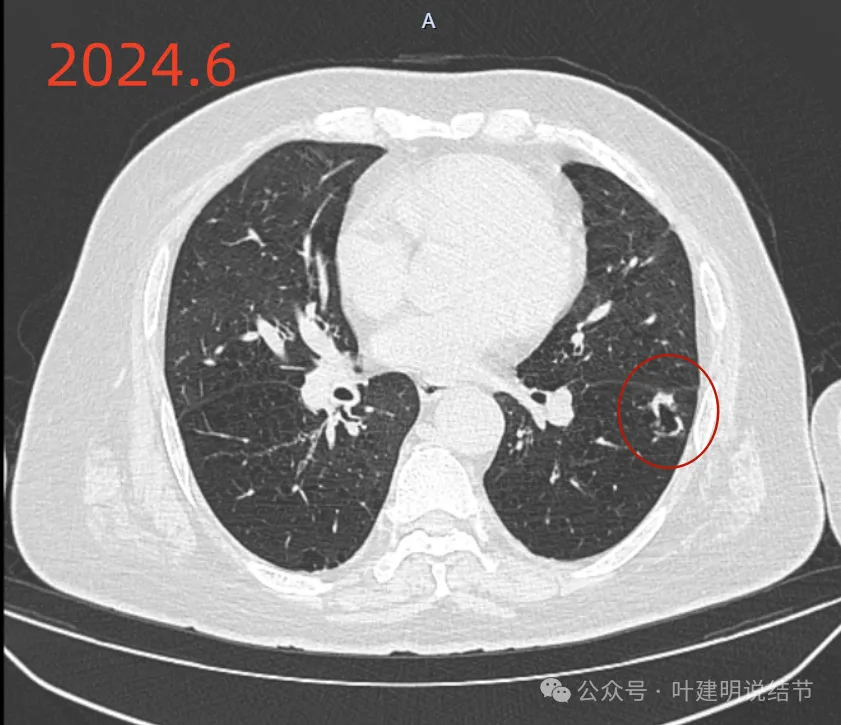

先看2024年6月的影像:

靠叶裂侧密度高、实性,灶内空腔多房,有微小血管走向并进入病灶的囊壁内,叶间裂有受牵拉。

囊壁明显厚薄不均,内壁也不光滑,而整体轮廓与边界却较为清楚。

部分边缘有细毛刺样征、中间密度低些,边上有囊腔,有的地方有少许磨玻璃成分,见到有小血管多处进入病灶。